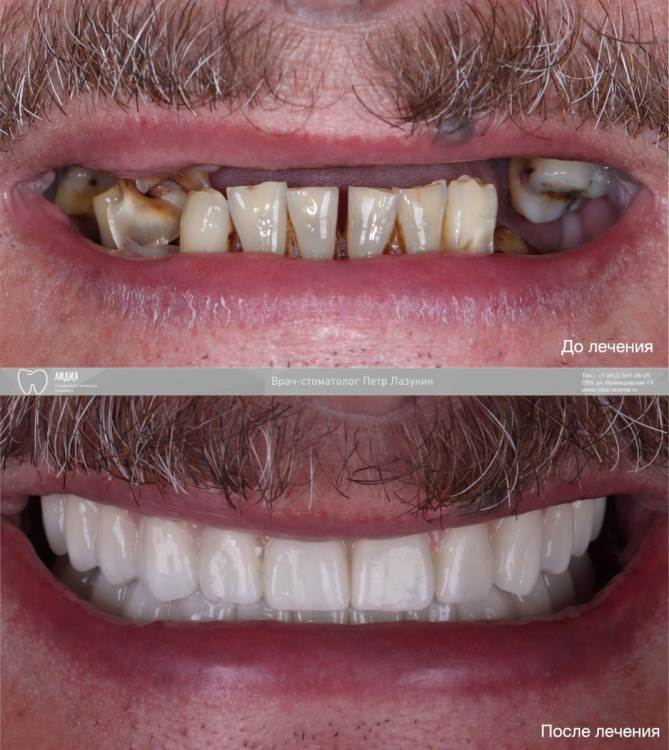

pit Опубликовано 9 августа, 2023 Поделиться Опубликовано 9 августа, 2023 Всем привет! Клинический случай тотального протезирования с опорой на имплантаты. Немедленная имплантация верхней и нижней челюсти с интервалом в 2 месяца. На верхней челюсти редукция, имплант 25 зуба транссинус. Отсроченная нагрузка, так как треснул гребень. Видео операции здесь https://youtu.be/YZM-A8we1WQ Постоянное протезирование ДЦ коронками с тирановыми каркасами. Верх с уровня МЮ, низ с уровня платформ. 2.mov 7 1 3 Ссылка на комментарий